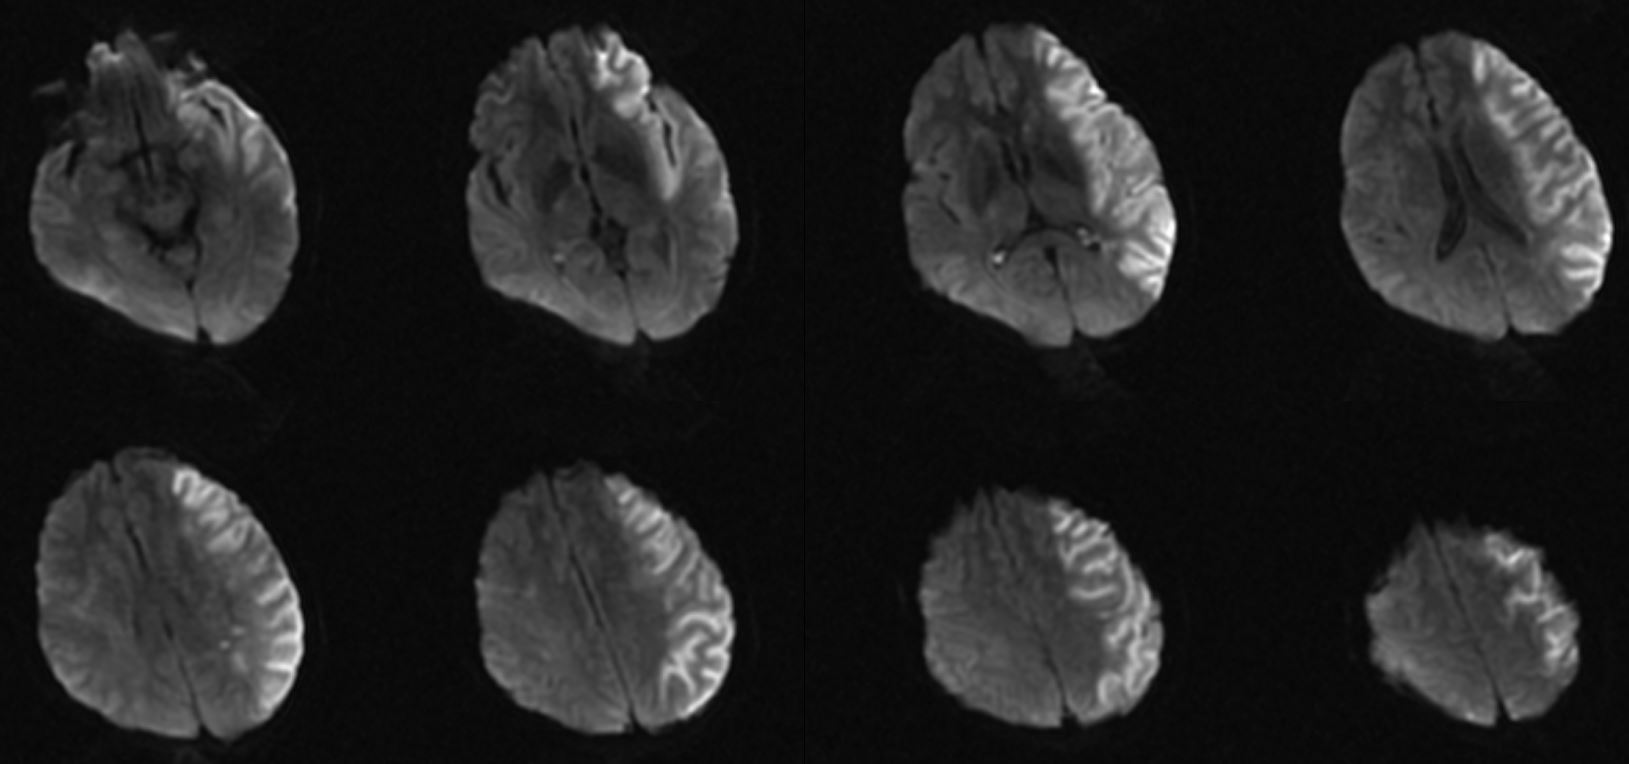

虽CTA提示颅内段颈内动脉及左侧颈内动脉颅内分支无明显缺失,但大脑中动脉远端分支明显稀疏,显影不佳。再结合头颅磁共振了解代谢情况。

术后当天麻醉苏醒顺利,右侧肢体活动较术前好转,能抬离床面,考虑大面积脑梗死,术后予单抗、他汀、清除自由基等治疗。

复查CT无出血,无造影剂外渗,病灶范围较大,侧脑室受压,适当脱水,控制颅内压,考虑大面积梗死,又是ICAS,选择使用单抗。

此次复查患者颅内水中完全消退,片中所示低密度灶范围较术前明显减少,结合患者症状表现,患者明显获益。